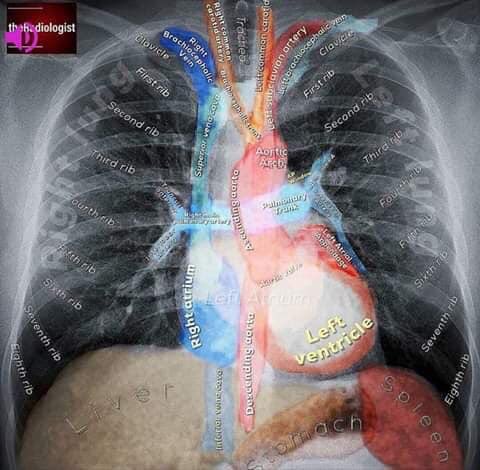

Do you recall your anatomical structures? #anatomicalstructures #pulmonary #medicine #respiratory #RTpowerpoints